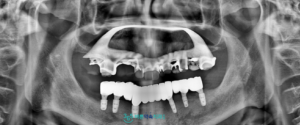

정밀 진단을 위해

파노라마 촬영을 진행한 결과,

아래턱 잔존 치아 주변의 잇몸뼈가

많이 감소하여 치아를 지지하기

어려운 상태로 확인되었고,

발치가 필요한 상황이었습니다.